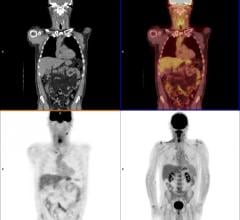

September 7, 2017 — Advanced melanoma has a poor prognosis, but immune checkpoint inhibitor therapy can be effective for ...

Augmenix Inc. announced that Palmetto GBA LLC — the Medicare Administrative Contractor (MAC) covering North Carolina, South Carolina, Virginia and West Virginia — will establish coverage for SpaceOAR hydrogel when medically necessary, effective Oct. 2, 2017. The change will enable Medicare beneficiaries in these states access to SpaceOAR hydrogel for use in prostate cancer radiotherapy.